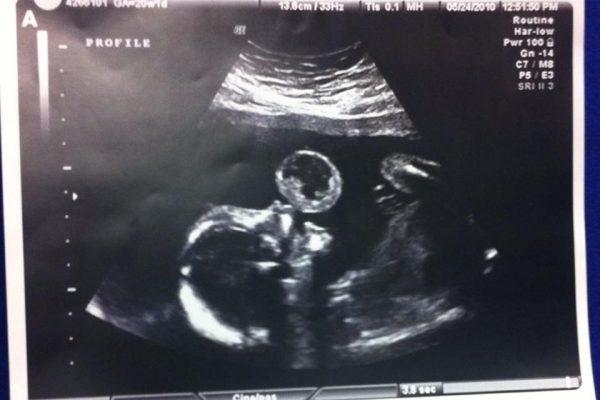

When Leyna, meaning “little angel,” was in her mother’s womb at 17 weeks of gestation, doctors discovered something strange during an ultrasound scan—they saw a “bubble” blowing from the unborn baby’s soft palate.

“Is that on me or the baby?” asked mom Gonzalez, as she stared at the ultrasound monitor, according to ABC News.

The doctors later confirmed the bubble was actually teratoma, a rare and potentially fatal oral tumor, developing in 1 in every 100,000 pregnancies. “They told me that type of tumor can grow so fast,” said Gonzalez.